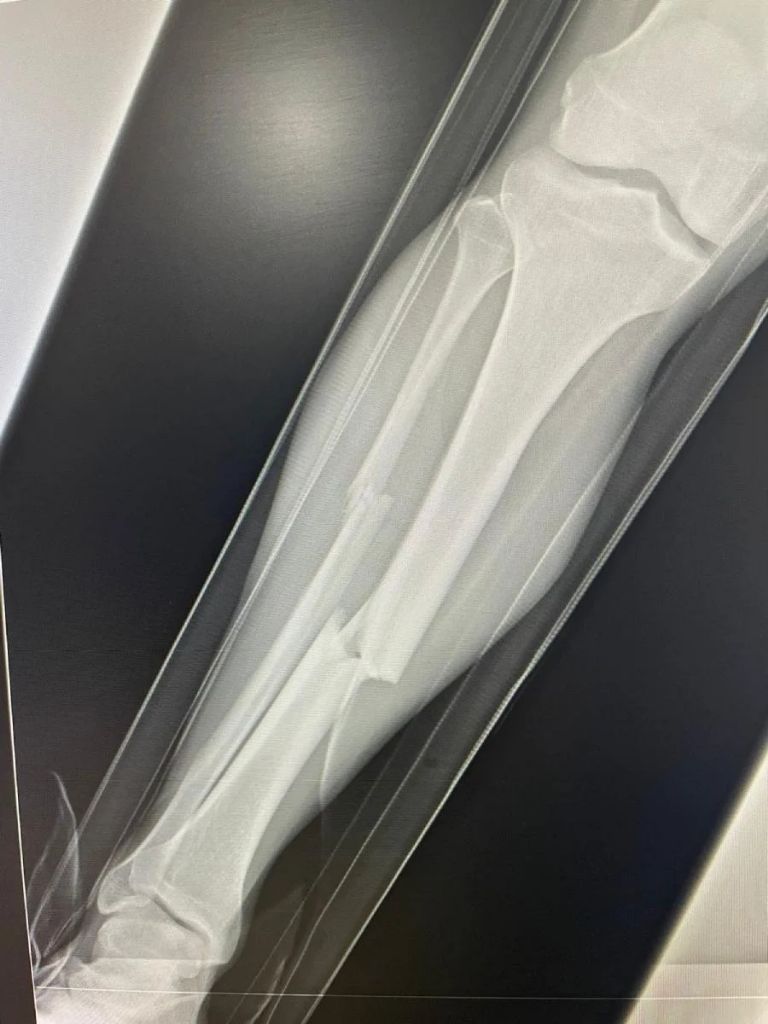

Ante la mirada atónita de jugadores y cuerpos técnicos de ambos equipos, el futbolista de los Potros de Hierro fue sacado en camilla con la pierna deshecha, lo que hacía preveer una dura y dolorosísima lesión que después se hizo realidad: fractura de tibia y peroné, por lo que la recuperación del jugador tomará varios meses.

La lesión propinada al carismático futbolista del Atlante causó enojo e indignación entre la afición y medios de comunicación, que en redes sociales han pedido la inhabilitación del zaguero de los Dorados de Culiacán y cómo no si en las imágenes compartidas por los Potros de Hierro se observa un ligero desplazamiento de los huesos que requerirá de una cirugía para comenzar su recuperación.